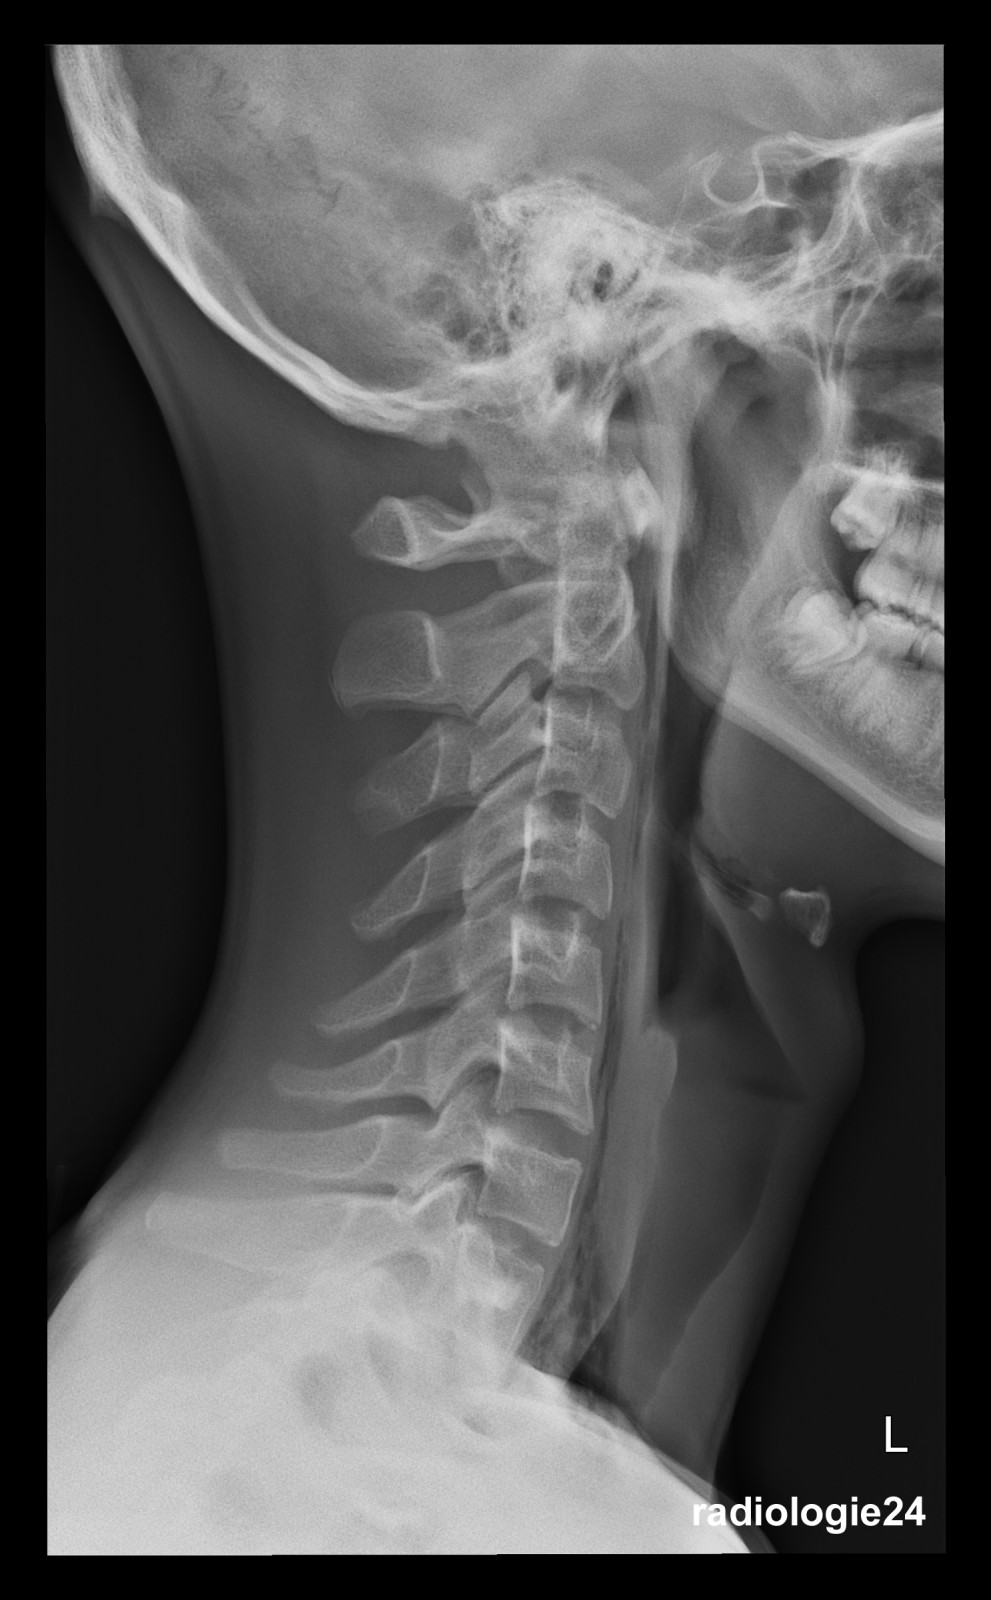

Röntgenfall des Monats Januar 2018 mit Auflösung

17 jähriger Patient

Sturz auf den Rücken beim Crossbiken. Schmerzen HWS und Thorax.

Fraktur, Pneumothorax, andere Pathologien?

Weitere bildgebende Diagnostik? Welche? Warum?